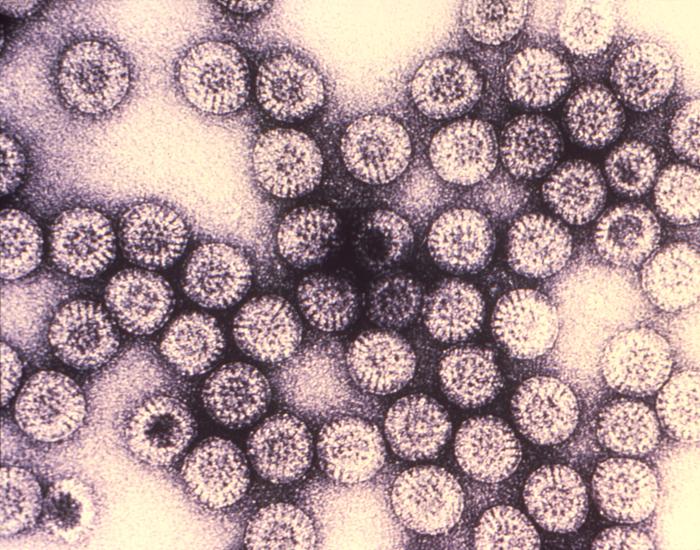

Rotavirus

Rotavirus is a stomach virus that causes severe diarrhea, vomiting, and fever in babies and young children, and the danger is dehydration. Small bodies lose fluids fast, and without treatment, the condition can become life-threatening within days. Before the vaccine became available in 2006, doctors called it “winter vomiting syndrome.” Because it tore through pediatric wards every cold season. Almost every child in the United States encountered the virus at some point. The numbers from that era are hard to forget. About 70,000 young children were hospitalized, and around 50 died from rotavirus each year in the U.S., according to CDC data cited by NPR. Pediatrician Sean O’Leary of the University of Colorado described it as “a miserable disease that we hardly see anymore,” and that rarity is a direct result of vaccination.

The virus has not disappeared. It still lives on the surfaces babies touch, from toys to changing tables, and it spreads easily in childcare settings. Vaccination rates have kept it in check, but infectious disease specialists warn that lower rates will bring back the hospitalizations. The infrastructure that once handled tens of thousands of sick babies each winter no longer operates at that scale. Which means a resurgence would hit hospitals that are no longer prepared for it.

Rotavirus is violent and fast, a disease of the gut that typically resolves within days. The next two vaccines on the list target a different organ entirely, and the consequences of infection can take decades to appear.